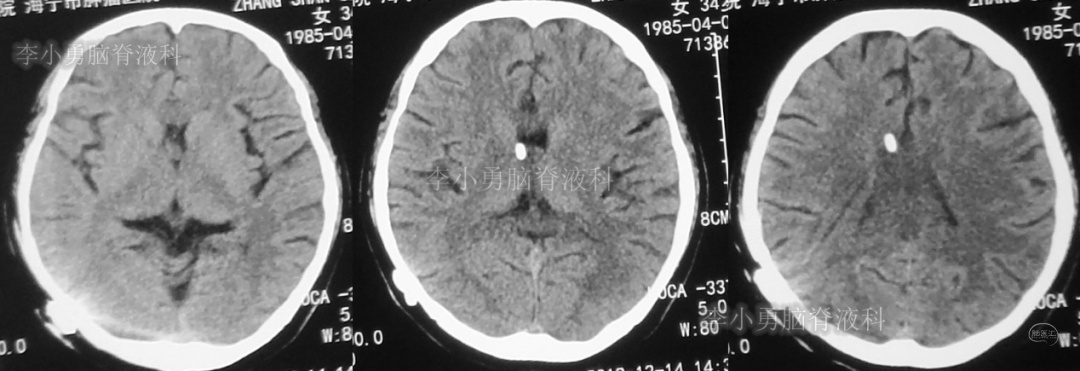

此后1个多月(2019年11月4日到2019年12月16日),患者意识一直无改善,一直呈模糊状态,多次复查头颅CT(图-12至图-20)见脑室大小反复变化不定,医生根据CT结果等反复多次调节分流泵压力(具体过程家属回忆不起)。但患者病情无好转却逐渐加重,逐渐不能咀嚼、吞咽及进食,卧床不起。

图-18:2019年12月13日头颅CT

图-19:2019年12月14日头颅CT

图-20:2019年12月16日头颅CT